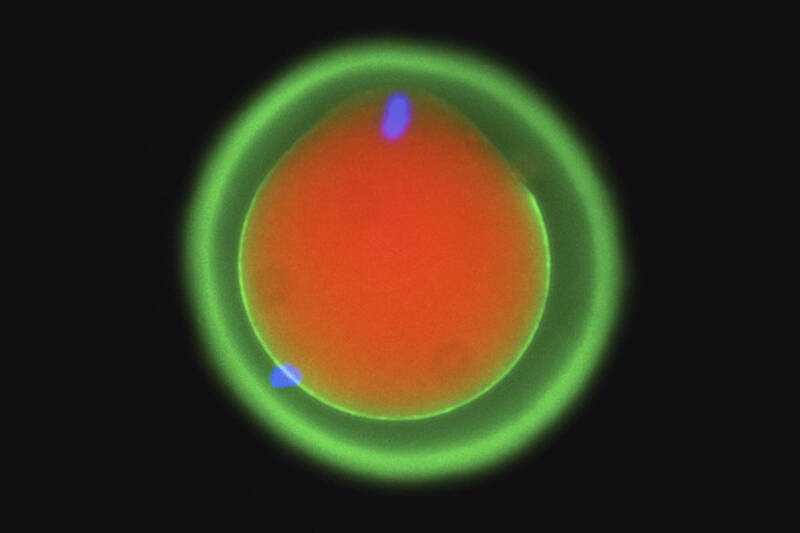

人类受精过程像“钥匙解锁” 让精子能附在卵子上

(维也纳19日综合电)奥地利科学家发表研究报告,揭开动物受精过程的奥秘,声称精子和卵子的结合,就像钥匙解锁,而且从鱼类到人类的脊椎动物都是如此。

《美联社》报道,这份在《细胞(Cell)》期刊发表的研究,是根据在斑马鱼、老鼠和人类细胞上所做研究,发现受精是精子上3种蛋白质,一起形成一种类似钥匙的机制,“解锁”卵子,让精子得以附著在卵子上,从鱼类到人类都是如此。报告共同作者维也纳“分子病理学研究所”(IMP)发育生物学家鲍利指出,“我们发现,这种确实是在所有脊椎动物身上的基本机制。”

过去科学家已知有2种蛋白质与受精作用有关,一个是在精子表面,另一个是在卵子的细胞膜上。鲍利这份与国际研究人员合作的研究,透过日前才获得今年诺贝尔化学奖的人工智慧技术协助,找出第3种蛋白质。

研究人员利用谷歌旗下DeepMind人工智慧工具AlphaFold,辨识出另一种新的蛋白质,让精卵建立首次分子连结,并且在活体生物上呈现此机制如何运作。鲍利说,之前并不知道这些蛋白质“像一个团队一样,携手合作,让精子和卵子辨识出彼此。”